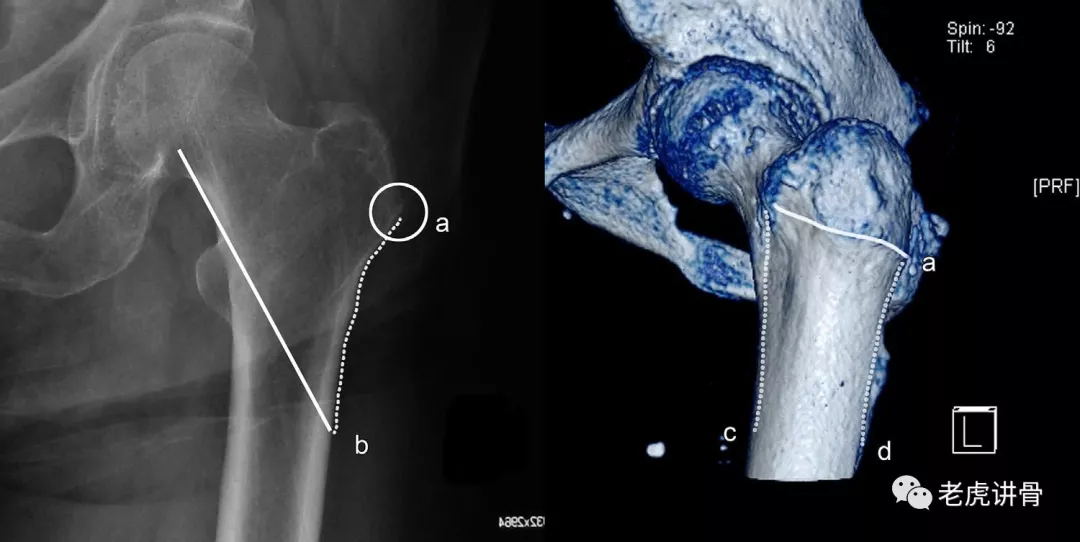

左侧x线,ct,股骨近端多段粉碎骨折,又称股骨粗隆下骨折;ao分型:32c3i